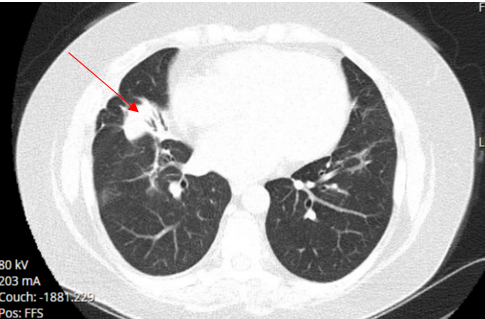

The patient's repeated CT chest without contrast after one year of antifungal therapy showed stable subtle tree-in-bud nodularity in bilateral upper lobes and small localized consolidation in the right middle lobe with a small air bronchogram which has a configuration suggesting round atelectasis and stable appearance of bilateral pulmonary nodularity (Figure 15). However, the infiltrate has improved significantly compared to previous images taken a year ago at the time of diagnosis.

Figure 15. CT chest one year after antifungal therapy showing rounded atelectasis in right middle lobe.